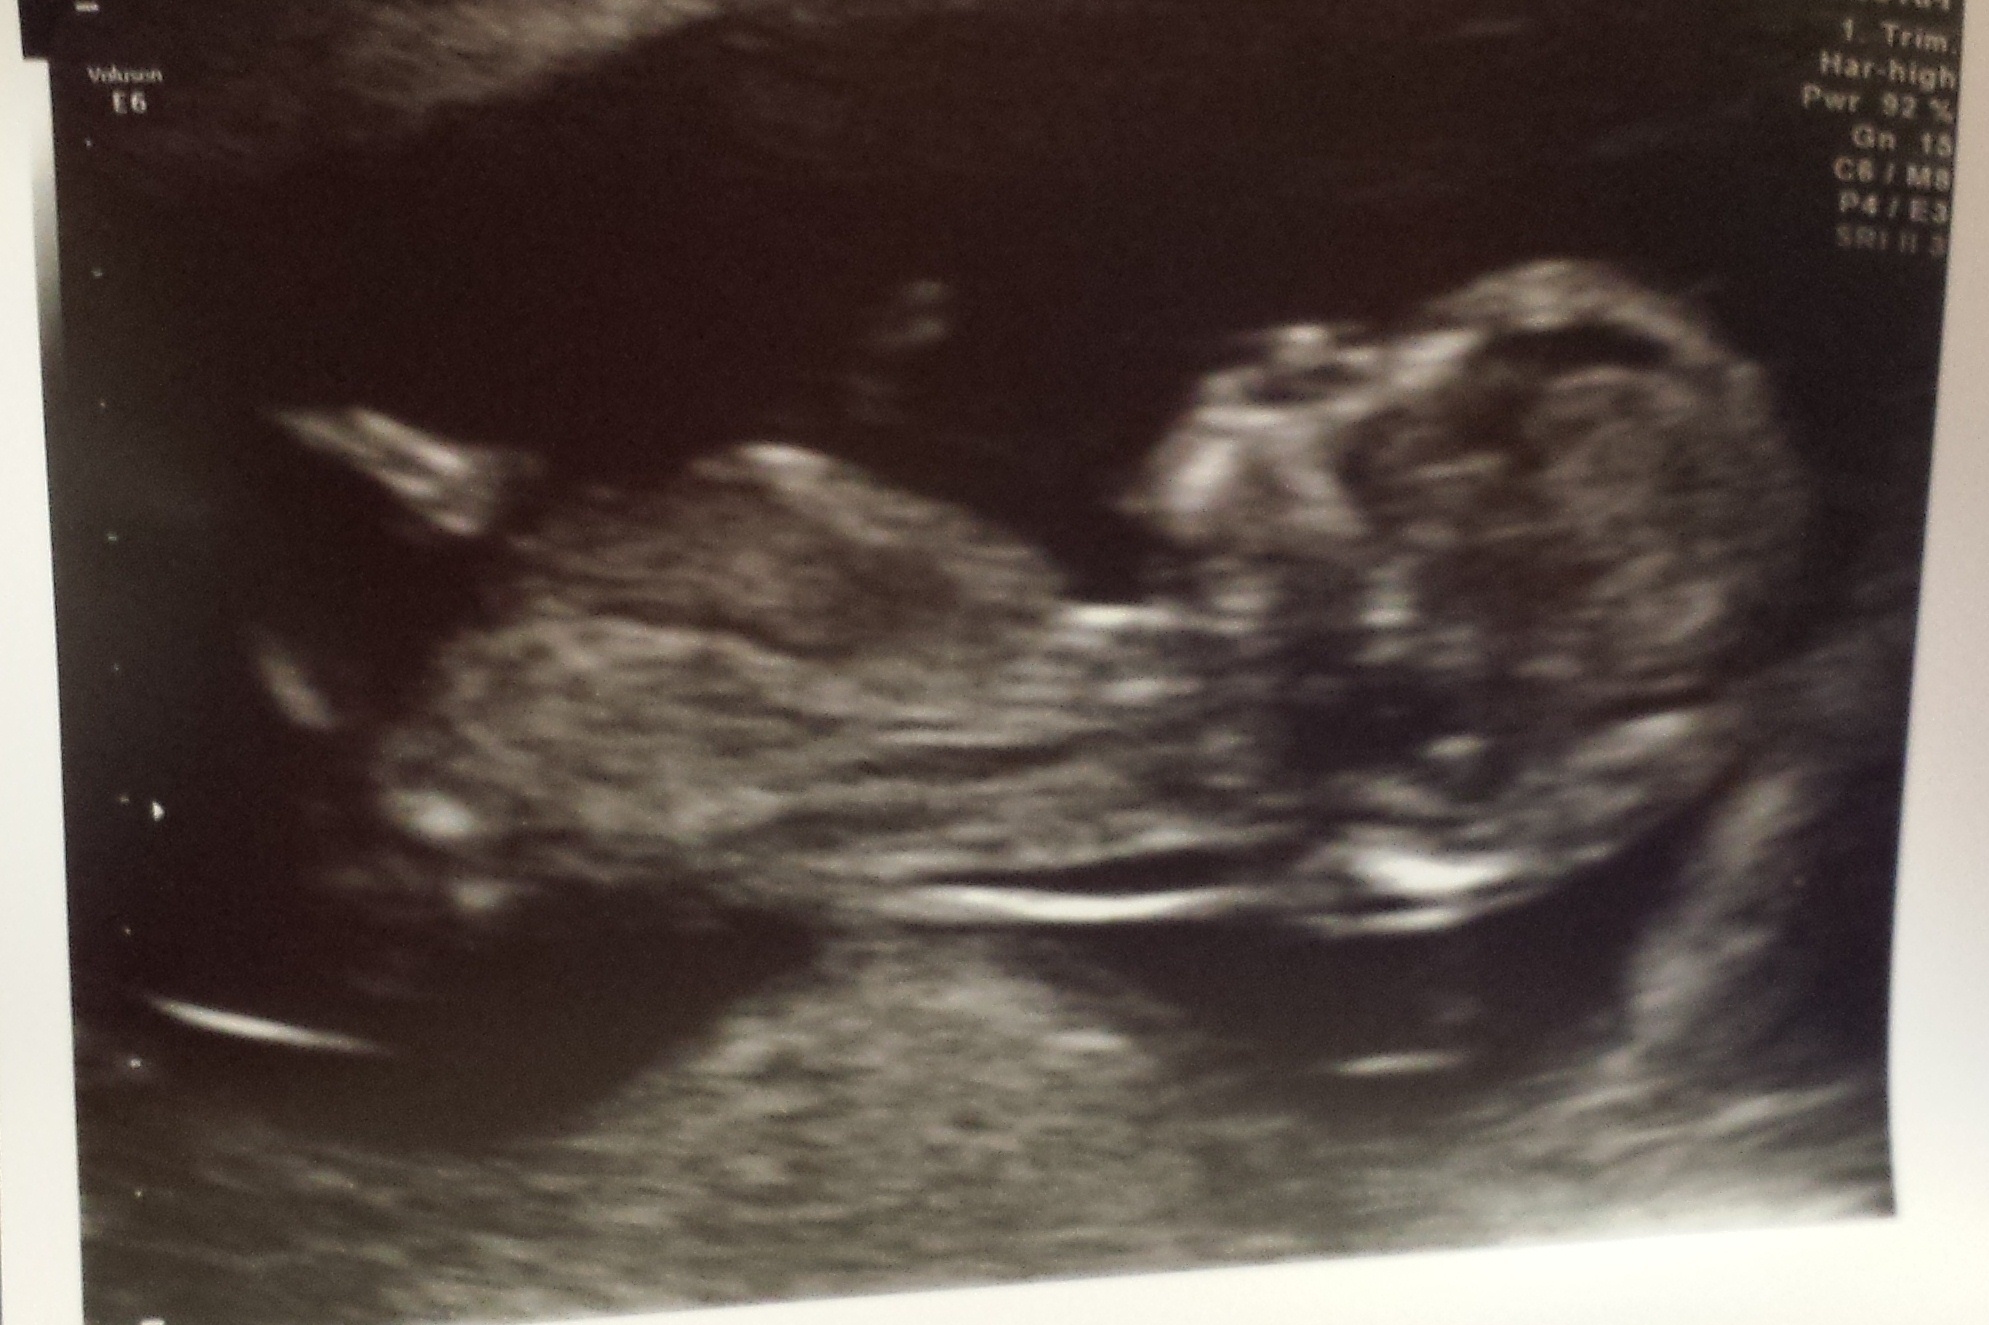

I have only just come across the nub theory and would love if anyone could give me an opinion on my scan at 12weeks and 4days?

I think I can see the nub on the last picture. I'm not very good but would go for a slight girl lean.

Most of the others on here are much better at guessing then me. X